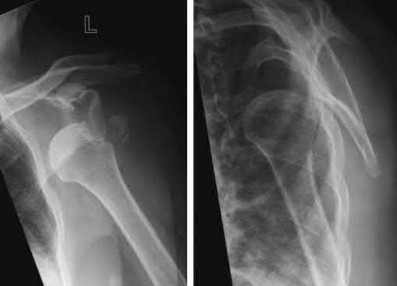

Question 12

A 55-year-old patient presents with a slowly enlarging, painful mass in the proximal humerus.

Biopsy reveals a hyaline cartilage matrix with cellular atypia, confirming a diagnosis of central conventional chondrosarcoma. Which of the following genetic mutations is most frequently identified in this specific tumor?

Explanation

Mutations in the isocitrate dehydrogenase genes, IDH1 and IDH2, are found in up to 50-60% of central conventional chondrosarcomas and enchondromas. EXT1 and EXT2 mutations are characteristic of multiple hereditary exostoses (osteochondromas). GNAS mutations are seen in fibrous dysplasia. TP53 and RB1 mutations are hallmark aberrations in osteosarcoma.